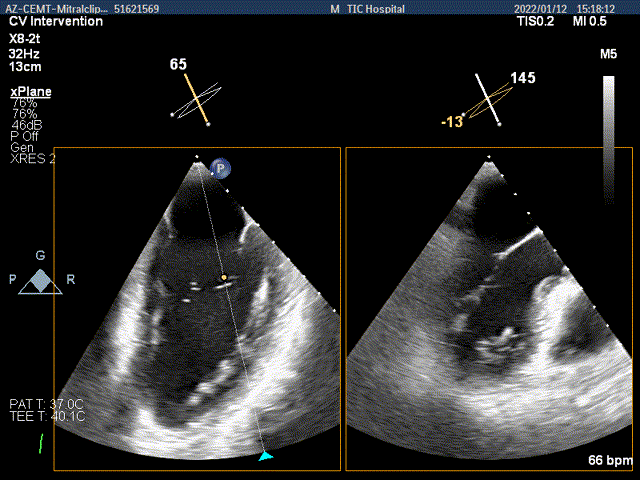

术前超声评估

术前超声诊断

Bicom:MR(重度),返流束宽12mm,返流面积10.3cm2,PISA法定量EROA:

0.77cm2,Rvol:115ml,RF:35%,r:12mm。

二尖瓣返流频谱呈全收缩期

肺静脉血流频谱呈收缩期反向

3D MV View:二尖瓣AC区为主(累及部分1区)脱垂并腱索断裂

3D-color MV view:大量返流,主要来源于AC区

Qlab软件勾画估测瓣口面积约:6.89cm2

二尖瓣口平均跨瓣压差:3mmHg

TEE Bicom view:二尖瓣AC区为主(累及部分1区)脱垂并腱索断裂。

Color-view:大量返流,主要来源于AC区